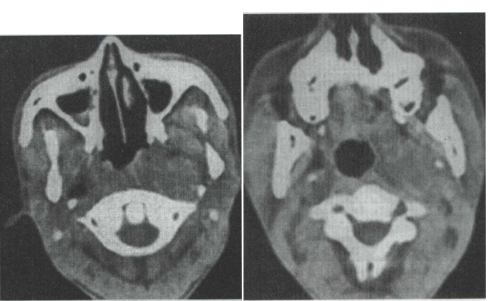

28.男性,50岁。涕中带血丝1个月余,无发热及咽部肿痛。CT检查见图所示,应首先怀疑以下何种疾病 ()